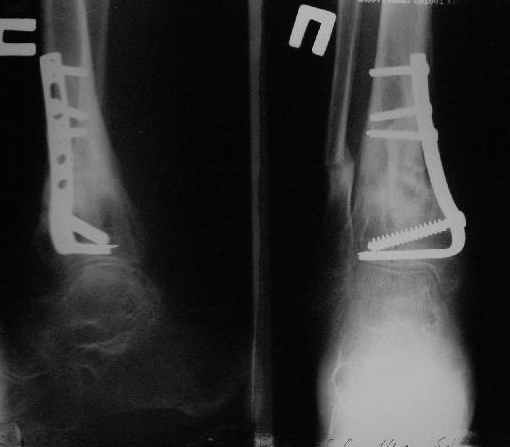

В январе 2005: варусная деформация н\3 голени, болевой с-м, комбинированная контрактура г\стопного сустава, нейропатия м\берцового нерва сохраняется слабость разгибания 1 пальца.

Операции: 1 Клиновидная резекция на вершине деформации м\берцовой кости.

2 Тугоподвижный ложный сустав н\3 б\берцовой кости. Рубцы выполняющие пространство между отломками, канал проксимального отломка иссечены.

Одномоментное устранение деформации, остеосинтез Г-образной пластиной.

Пластика по Хахутову.

Заживление проксимальной части раны вторичным натяжением без нагноения. Рана зажила. Спицы удалены через 1,5 недели после операции.

Особого смысла в них не было.

Учитывая фон (интеллект, etc) гипсовая повязка.